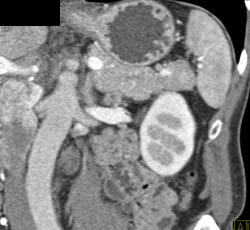

CTA of Pancreas